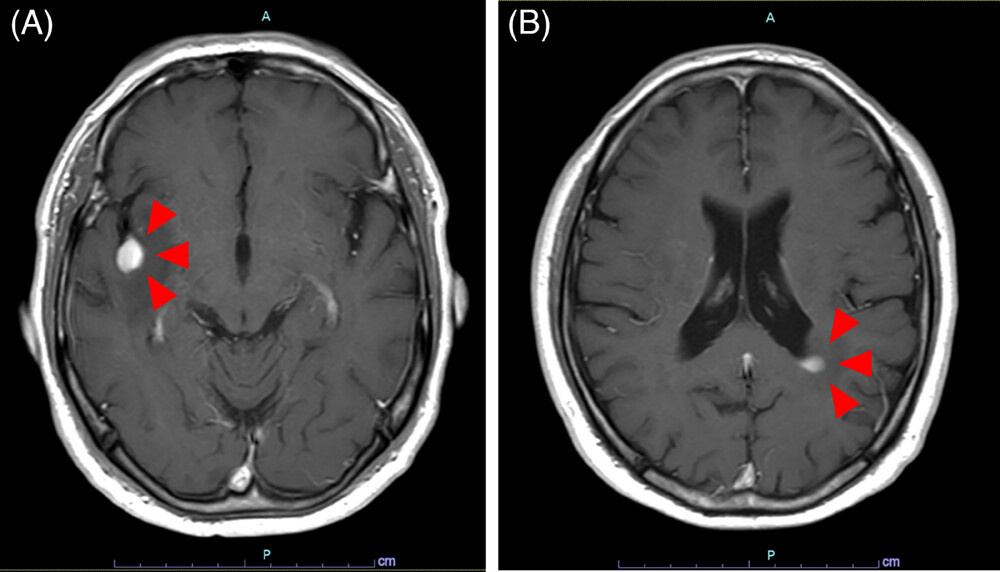

头部磁共振成像(MRI)显示右侧岛叶及左侧脑室旁白质存在肿块(图1A,B)。右侧岛叶肿块活检的病理分析显示,大脑组织中存在大量异型淋巴细胞浸润(图2A)。免疫组化结果显示,这些异型淋巴细胞CD3、CD4、CD30阳性,而CD8、CD20、ALK、EMA阴性(图2B–H)。这些发现与左肋区和左膝活检标本的结果一致。因此,诊断为PC-ALCL中枢神经系统复发。脑脊液中未发现淋巴瘤细胞浸润。皮肤病变仍处于缓解状态,且无其他系统性病变。

图2.钆增强T1加权MRI显示右侧岛叶(A,红色箭头)和左侧脑室旁白质(B,红色箭头)存在肿块病变